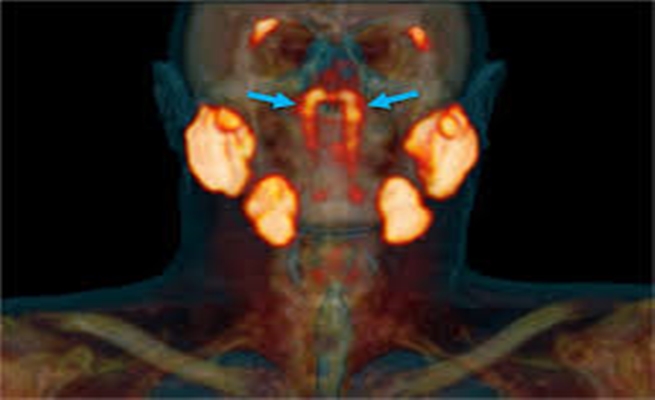

وجرى التعرف على هذا “الكيان غير المعروف” عن طريق الصدفة من قبل الأطباء في هولندا، الذين كانوا يفحصون مرضى سرطان البروستات بنوع متقدم من الفحص يسمى PSMA PET/CT. وعند إقرانها بحقن الجلوكوز المشع، حيث تُبرز أداة التشخيص الأورام في الجسم.

ويعد الاكتشاف الجديد الذي توصل إليه فريق فوغل، أكبر بكثير، حيث يُظهر ما يبدو أنه زوج من الغدد أغفل سابقا – على ما يبدو المجموعة الرابعة من الغدد اللعابية الرئيسية – تقع خلف الأنف وفوق الحنك، بالقرب من مركز رأس الإنسان.

ويقول المعد الأول للدراسة، جراح الفم ماتيس فالستار، من جامعة أمستردام: “تبين أن المنطقتين الجديدتين اللتين أضاءتا، لهما خصائص أخرى للغدد اللعابية أيضا. نسميها الغدد الأنبوبية، مشيرا إلى موقعها التشريحي فوق الطور البوقي”.

وشوهدت هذه الغدد الأنبوبية في فحوصات PSMA PET/CT لدى 100 مريض فُحصوا في الدراسة، كما أظهرت الفحوصات الجسدية لجثتين – ذكر وأنثى – البنية الثنائية الغامضة، وكشفت عن فتحات مجاري التصريف المرئية بالعين المجردة، نحو جدار البلعوم الأنفي.